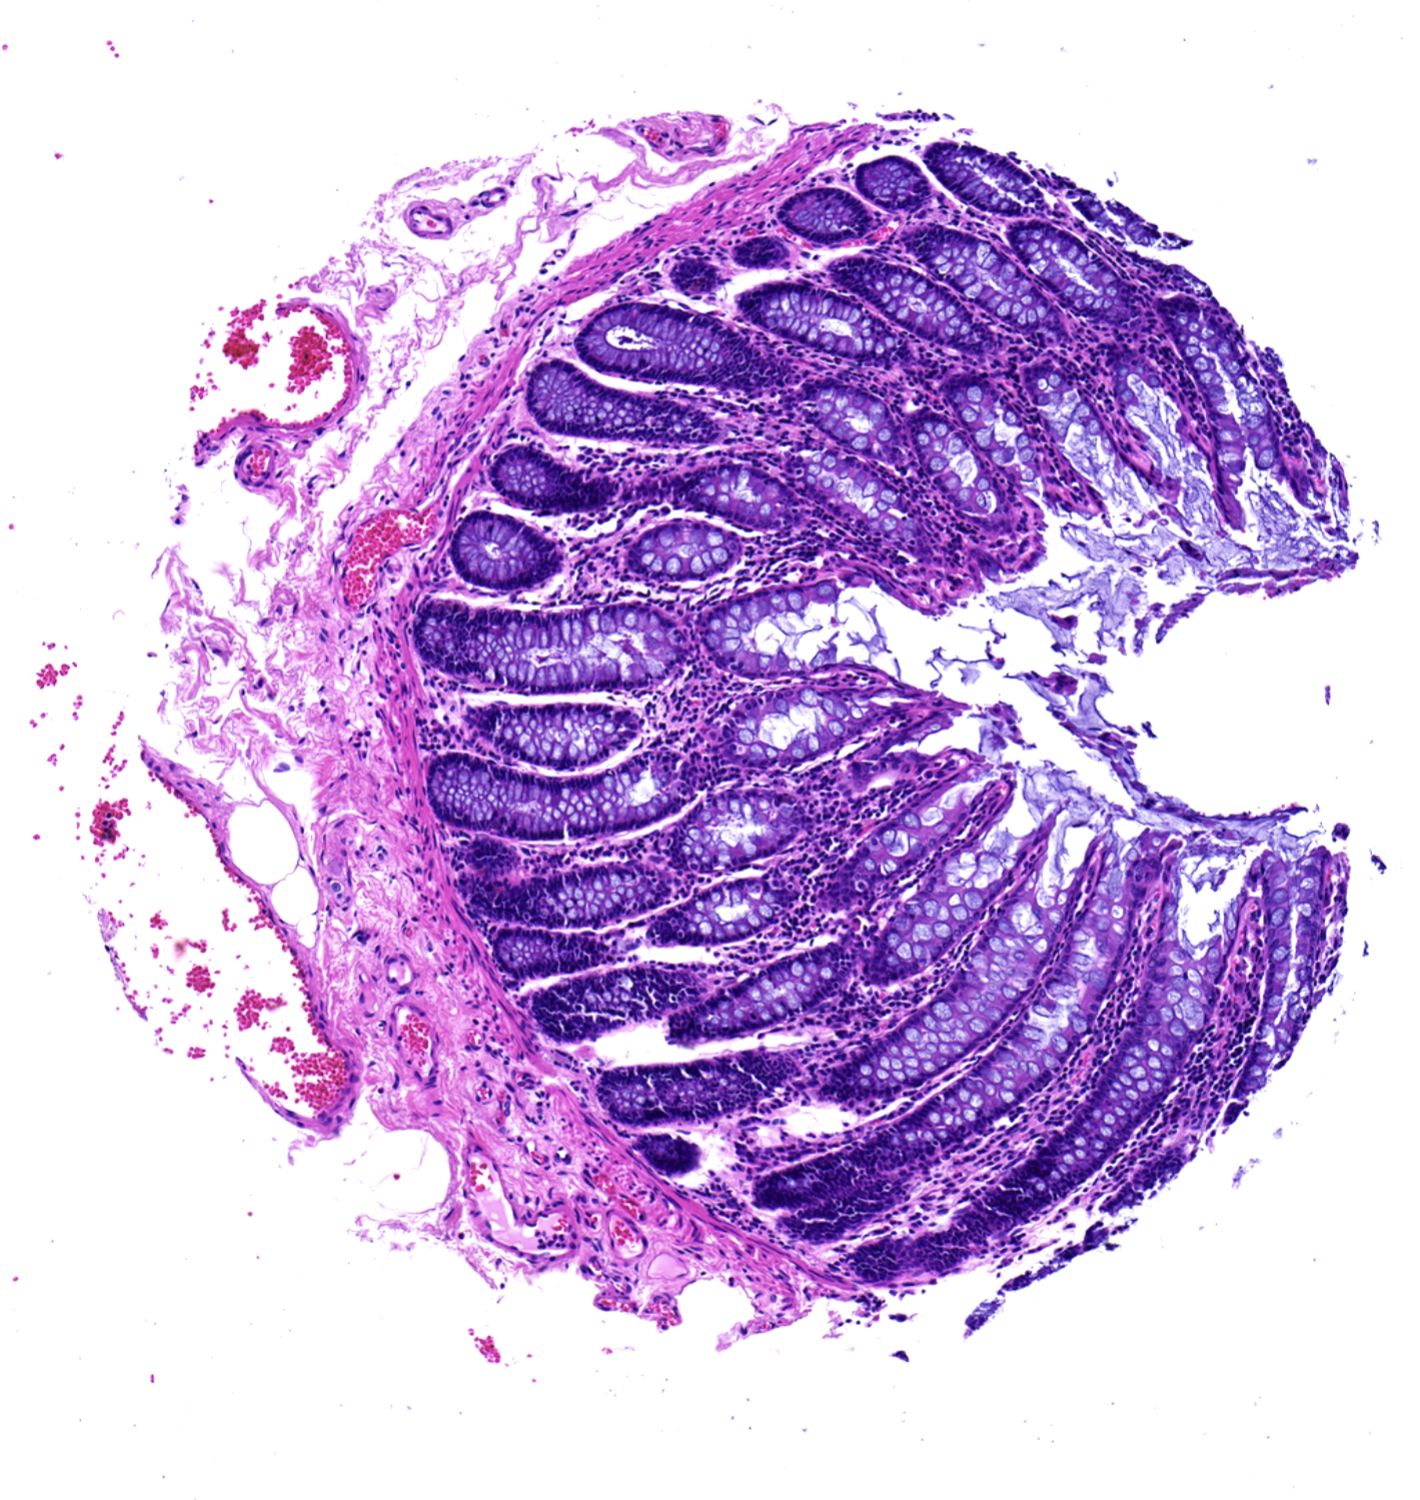

#4

Stain: Hematoxylin and Eosin

Tissue: Colon

Additional Information: Colorectal Adencarcinoma